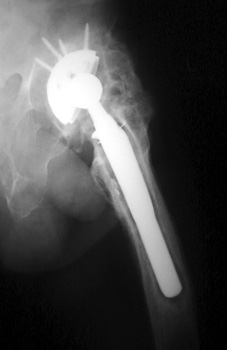

HETEROTOPIC BONE FORMATION adjacent to loose femoral component, plain film and CT